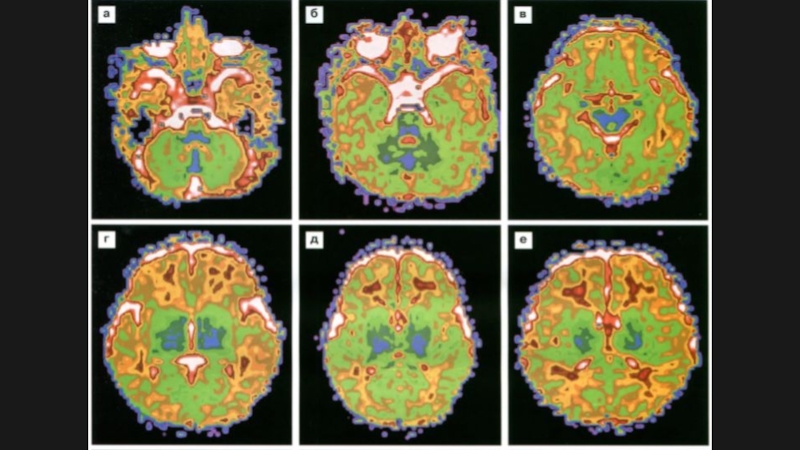

Слайд 1812 мес

2 года

12 мес2 года